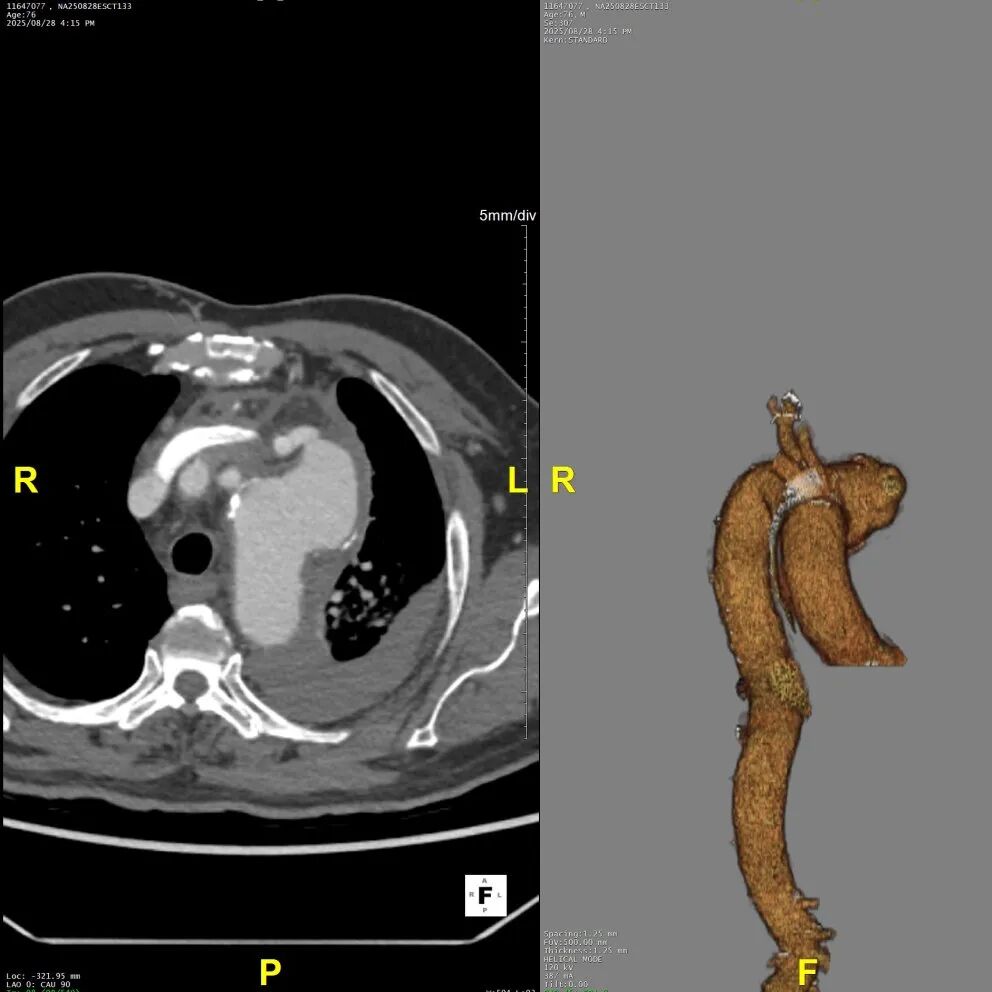

术后随访

术后病人恢复良好,康复出院。术后半年CTA如下,病人动脉瘤隔绝,弓上INA、LCCA血供稳定,LSA代偿良好,左上肢轻微无力。

考虑病人情况,II期行分支转流,重建LSA。

术后CTA

术后3D重建